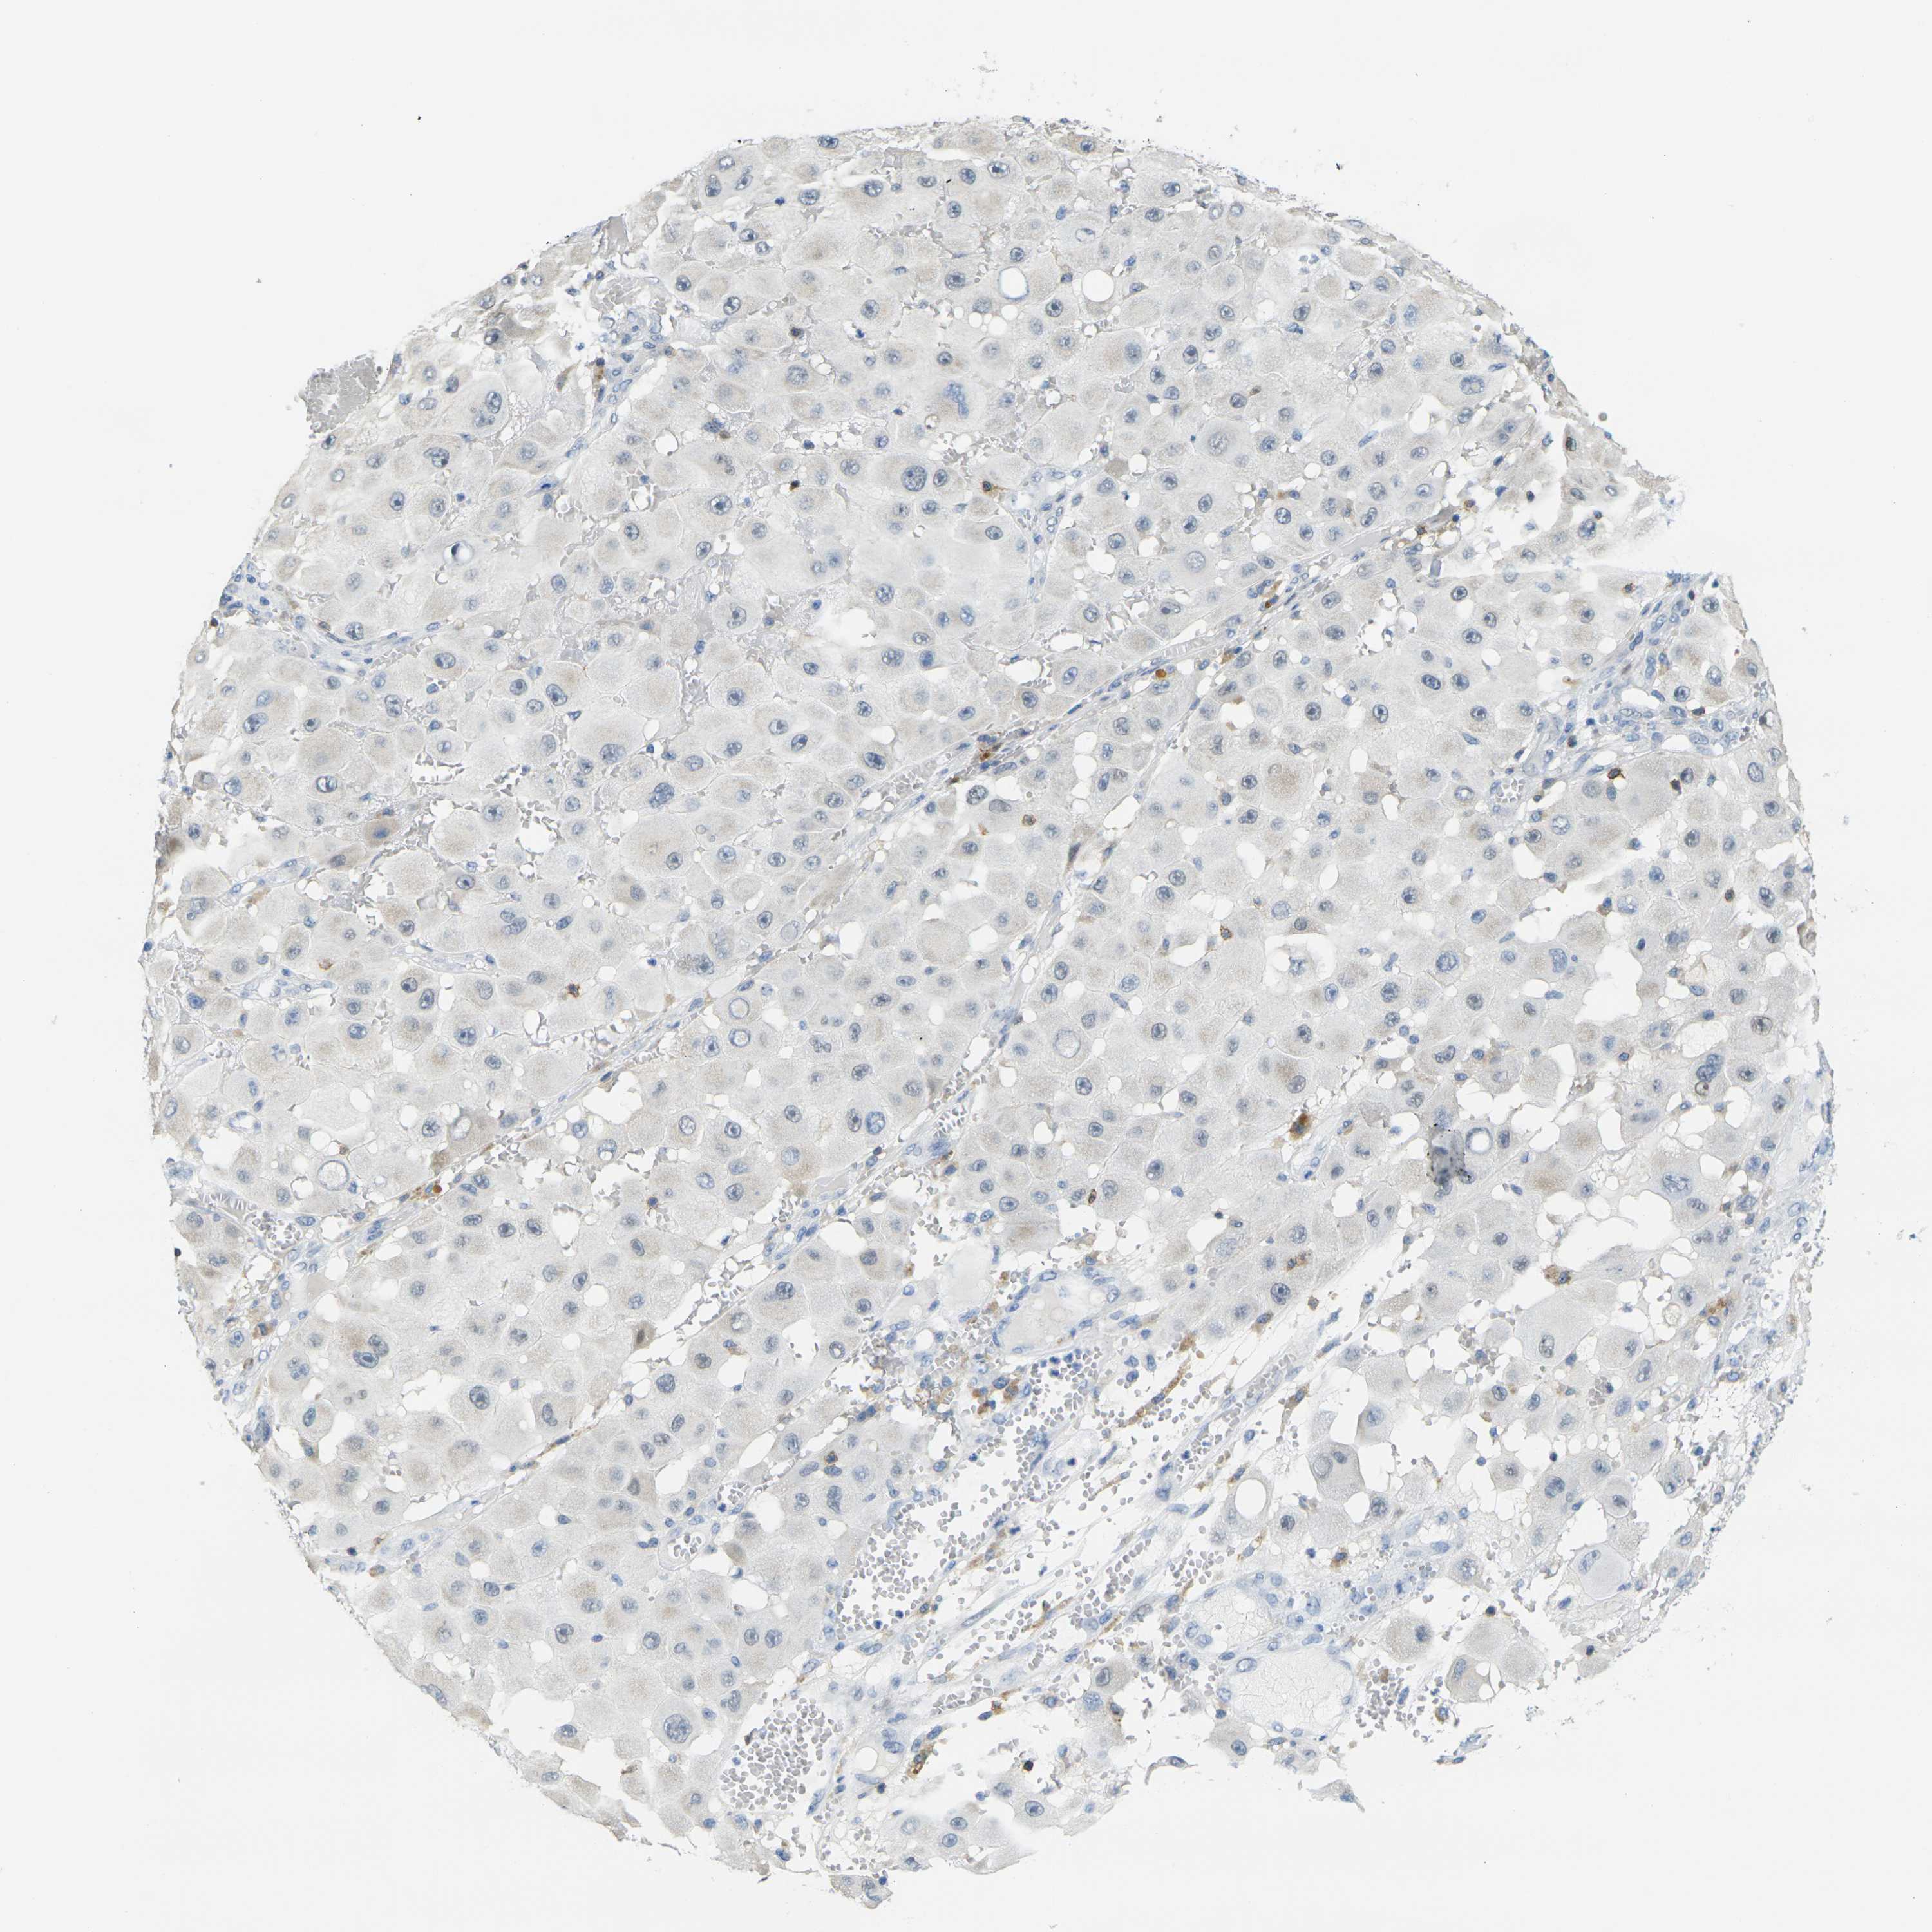

MELANOMA - Protein expressioni

A mouse-over function shows sample information and annotation data. Click on an image to view it in a full screen mode. Samples can be filtered based on level of antibody staining by selecting one or several of the following categories: high, medium, low and not detected. The assay and annotation is described here.

Note that samples used for immunohistochemistry by the Human Protein Atlas do not correspond to samples in the TCGA dataset.

Antibody stainingi

Antibody staining in the annotated cell types in the current human tissue is reported as not detected, low, medium, or high, based on conventional immunohistochemistry profiling in selected tissues. This score is based on the combination of the staining intensity and fraction of stained cells.

Each image is clickable and will lead to virtual microscopy that enables deeper exploration of all samples and also displays staining intensity scores, fraction scores and subcellular localization as well as patient and tissue information for each sample.

Antibody HPA071778

Antibody CAB013055

Malignant melanoma, NOS

Malignant melanoma, Metastatic site

Malignant melanoma in situ